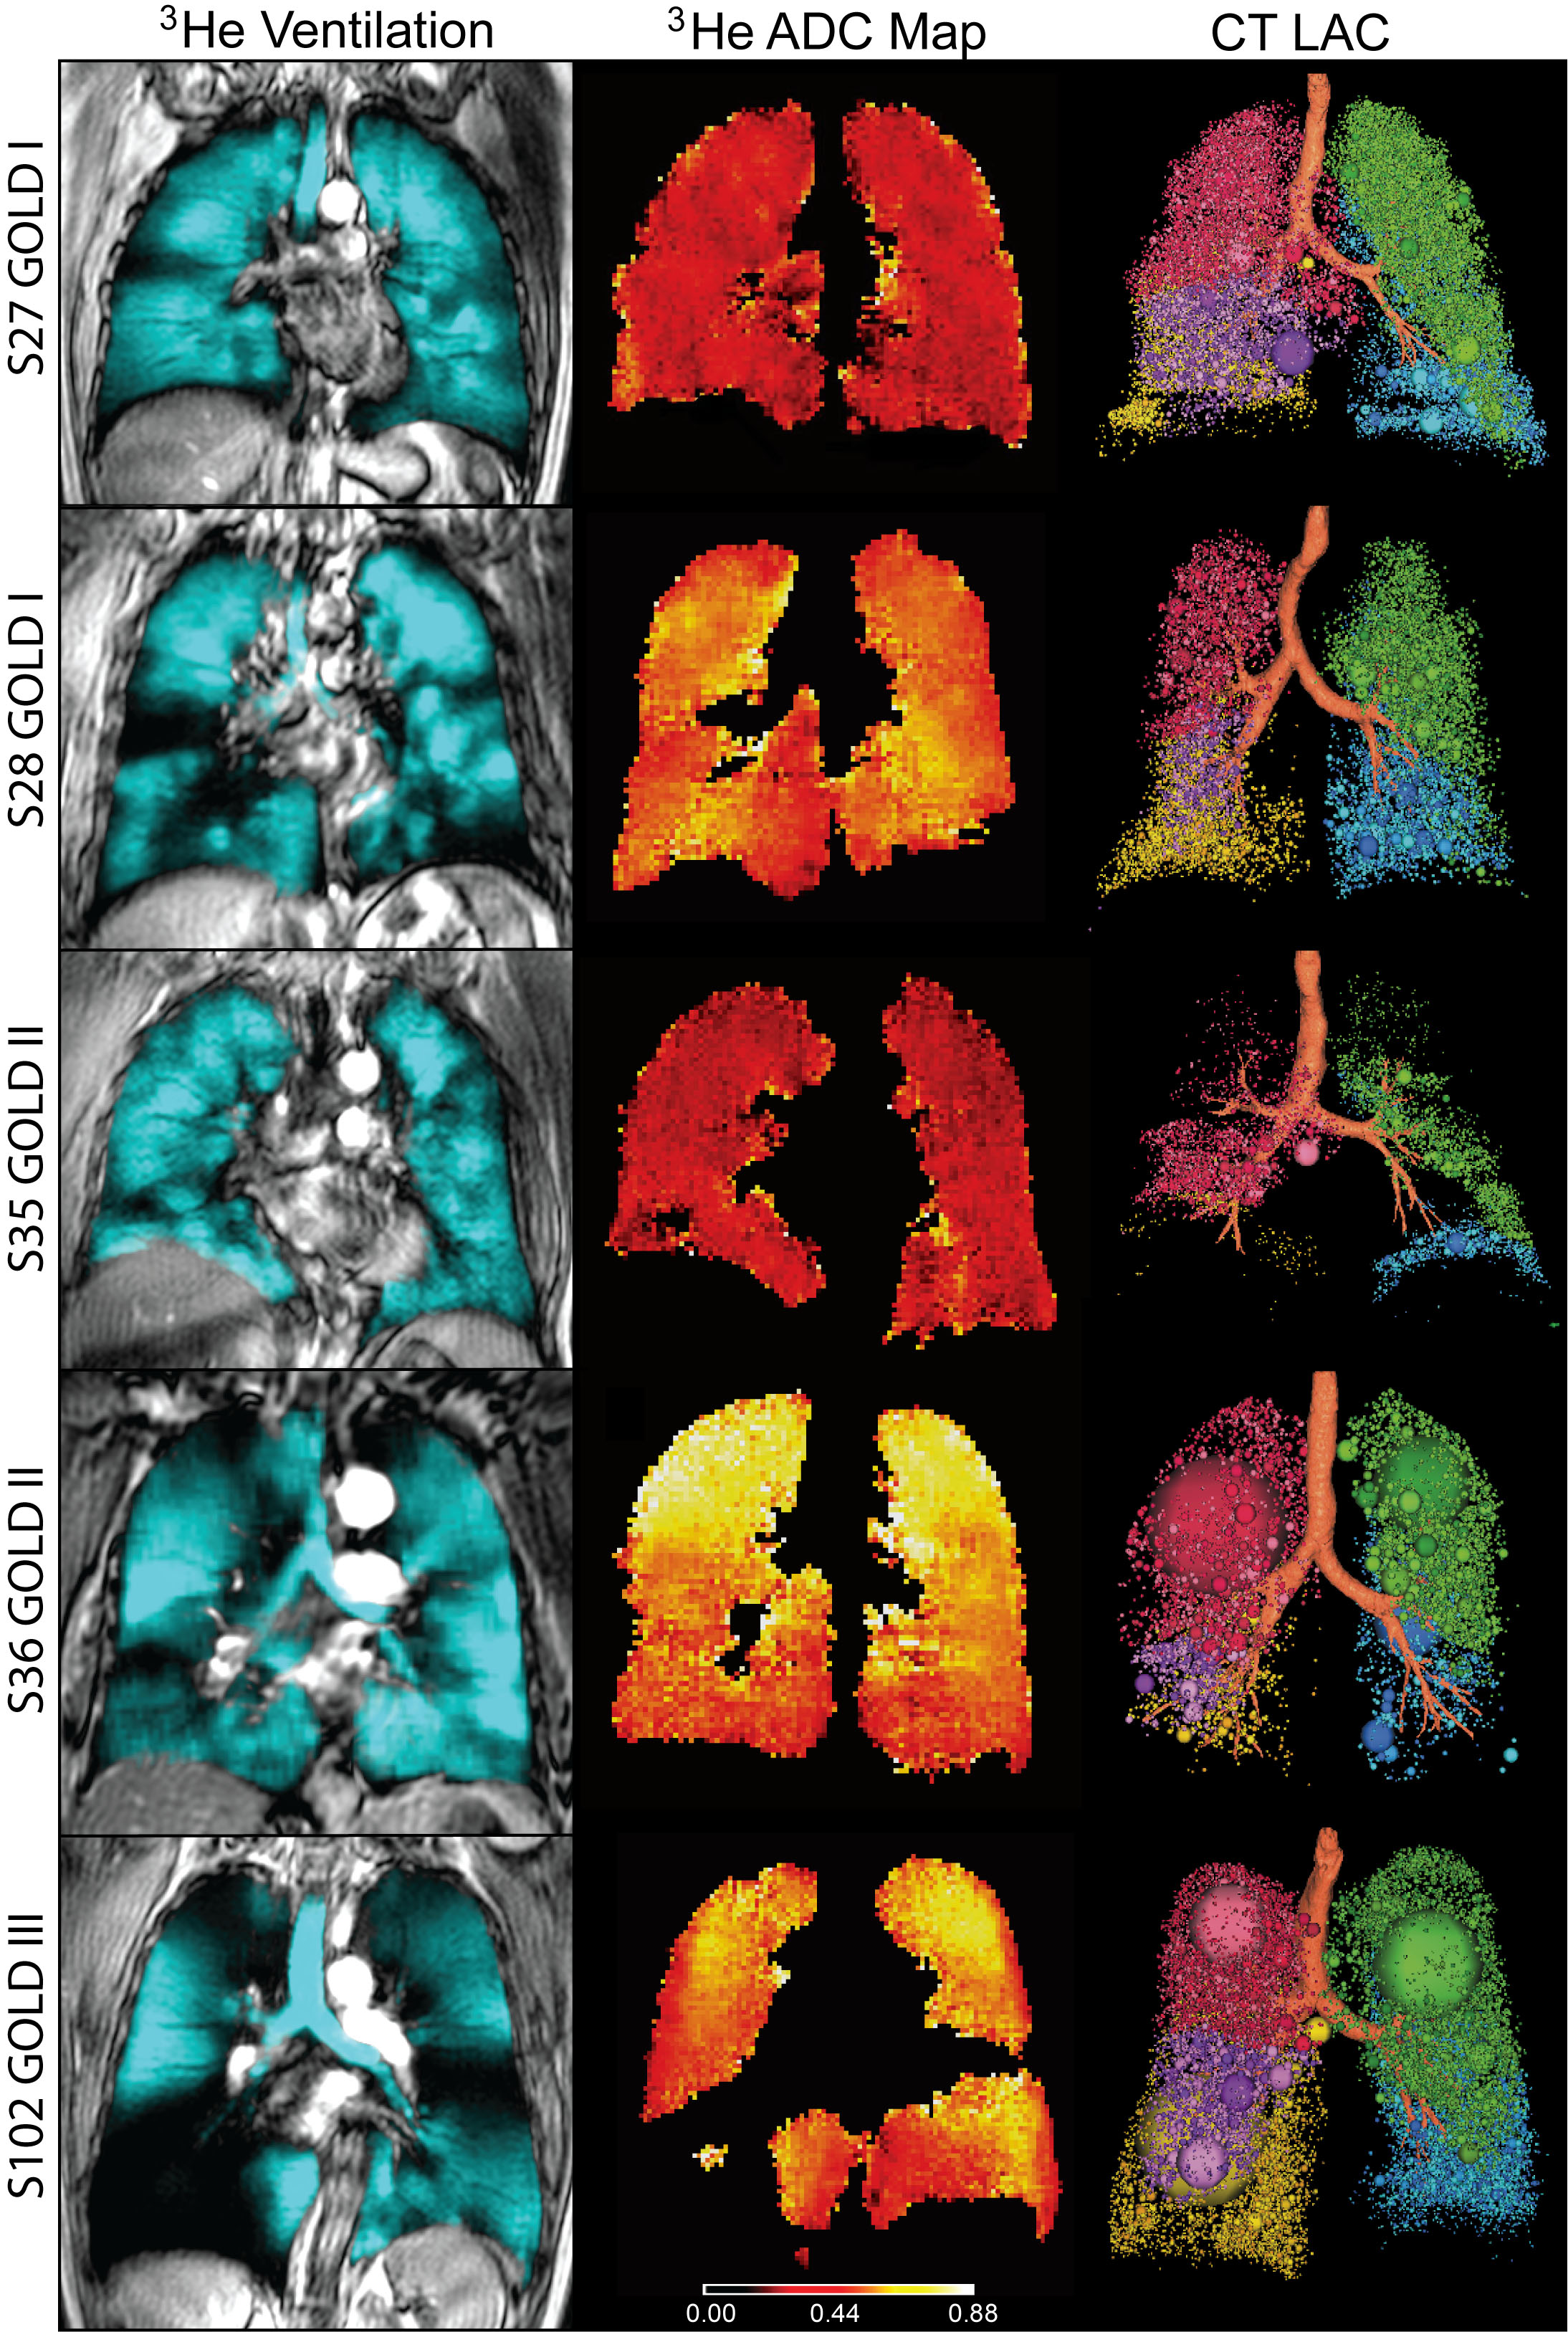

Researchers performed conventional CT and inhaled noble gas MRI, a technique for visualizing air spaces in the lungs, on 116 people with COPD, including 80 with milder disease. The patients also underwent lung capacity testing, filled out a quality of life questionnaire and took a six-minute walk to measure their exercise tolerance over a short period of time.

The results showed that in mild-to-moderate COPD patients with modestly abnormal FEV1, MRI measurements of emphysema were strongly correlated with exercise limitation, while both CT and MRI measurements of emphysema helped explain symptoms.